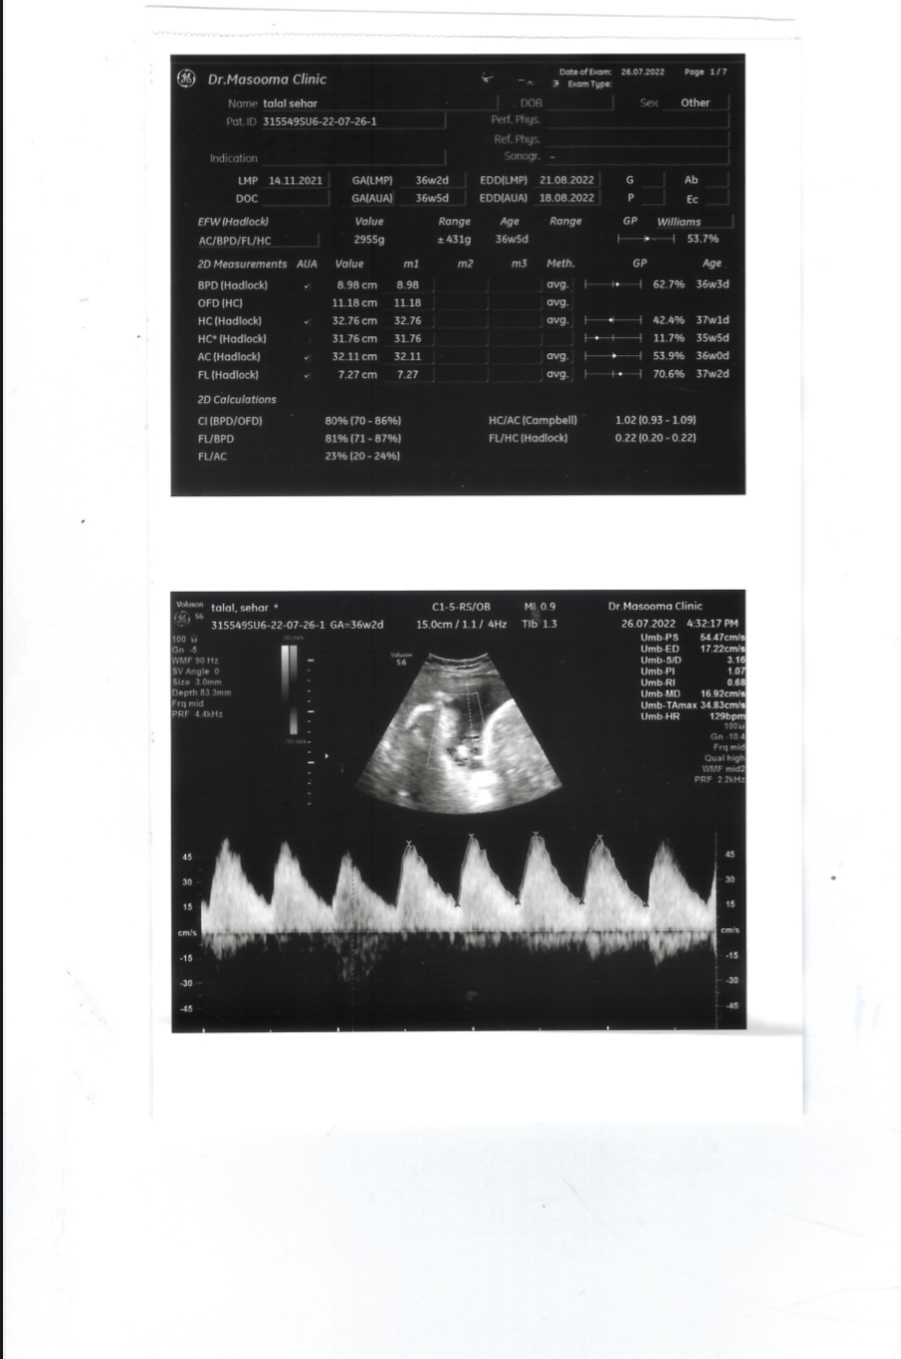

صحة السونار لحامل باسبوع ٣٦